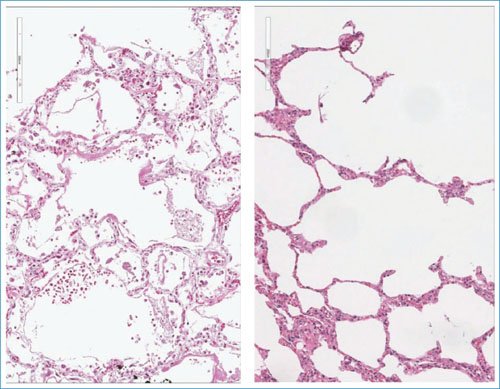

Figura 4. Comparación de los hallazgos histológicos en la influenza H1N1 y la COVID-19. El panel de la izquierda corresponde a una fotomicrografía de tejido pulmonar afectado por influenza H1 N1, que muestra daño alveolar difuso con formación de membranas hialinas y tejido de granulación intraalveolar; no hay notable daño intersticial ni microvascular (HyE, 20×). El panel derecho es una fotomicrografía que muestra tejido pulmonar afectado por COVID-19, con daño en las paredes alveolares caracterizado por neumonitis y obstrucción microvascular a expensas de microtrombos fibrinosos (HyE, 20×).